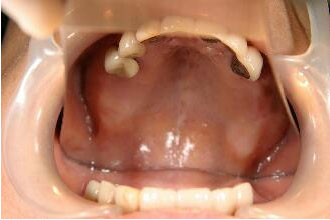

予定通り4ヶ月で最終かぶせ物(メタルボンドポーセレン)を装着。

この症例も十分咬合に耐える、しっかりした骨が形成されています。

・症例2同様、この新しいインプラントでは今までのインプラントのように複雑で、長い期間を必要

とする上顎洞への自家骨移植、人工骨添加は必要ないことがお分かりと思います

最終かぶせ物(メタルボンドポーセレン)を装着した口腔内写真 このあと右上上顎(上の写真では左の上となります)のインプラントを予定している。